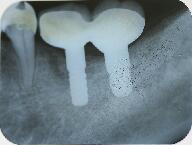

抜歯後エックス線写真

3ヵ月後の抜歯部

抜歯部位以外に手前に骨の吸収があるので抜歯同時のインプラント埋入手術は避けました